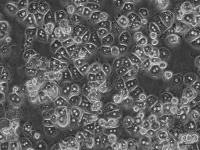

上皮样;多角形

贴壁生长

A-375人恶性黑色素瘤细胞描述:(1)所有细胞株购自ATCC;

(2) 公司可提供新鲜或冻存细胞株;

(3) 细胞株数量约 5×105/瓶;

(4) 不含有HIV-1、HBV、HCV、支原体、细菌、酵母和真菌。

A-375人恶性黑色素瘤细胞 保存和应用:客户可以根据自己的需求选择新鲜或者冻存的原代细胞,如是新鲜细胞株,客户收到细胞后应立即将其放入CO2细胞培养箱内静置后2-3h,再进行后续的实验操作。如是冻存细胞,客户收到细胞后应立即将其放入液氮、-80℃冰箱或立即进行复苏。A-375人恶性黑色素瘤细胞只用于科研,不得用于临床应用。